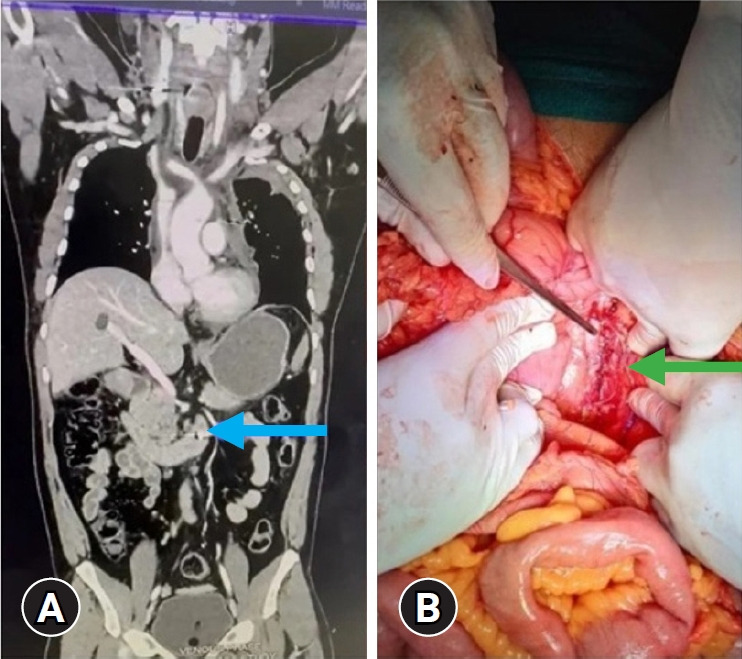

下腔静脉(IVC)损伤是罕见但致命的。根据损伤机制、患者状态和损伤类型的不同,干预可以是手术或血管内治疗。这些损伤通常在识别和治疗方面构成挑战。在手术干预期间,快速进入和及时控制出血部位可能是困难的。在本系列中,我们的目的是描述在我们中心出现的各种IVC损伤,详细介绍其管理的挑战和结果。本研究旨在描述在30个月的时间里,在一级创伤中心发生的下腔静脉损伤病例的表现、干预措施和结果。在本报告中,共有6例下腔静脉损伤在我中心治疗。所有患者均接受手术干预。每位患者均经历了高能创伤机制,其中3例为钝性创伤,3例为穿透性创伤。6名患者中,3人幸存,3人死亡。死亡的原因是延迟出现,损伤的复杂性和技术上的困难。坚持晚期创伤生命支持(ATLS)方案,及时诊断和复苏,快速决策可以降低下腔静脉损伤相关的死亡率。尽管如此,外科医生必须认识到处理这些损伤的固有挑战和陷阱。

Inferior vena cava (IVC) injuries are rare but deadly. Depending on the mechanism of injury, patient status, and type of injury, intervention may be surgical or endovascular. These injuries typically pose challenges in identification and treatment. During surgical intervention, rapid access and timely control of the bleeding site may be difficult. In this series, we aim to describe various IVC injuries presented at our center, detailing challenges and outcomes in their management. The study aims to characterize the presentation, interventions, and outcomes of IVC injury cases at a level I trauma center over a period of 30 months. In this report, a total of six cases of IVC injury were treated at our center. All patients underwent surgical intervention. Each patient experienced a high-energy trauma mechanism, with three patients sustaining blunt trauma and three sustaining penetrating trauma. Of the six patients, three survived while three died. Mortality was attributed to delayed presentation, complexity of injuries, and technical difficulties. Adherence to Advanced Trauma Life Support (ATLS) protocols, timely diagnosis and resuscitation, and rapid decision-making can reduce mortality associated with IVC injuries. Nonetheless, surgeons must remain cognizant of the inherent challenges and pitfalls in managing these injuries.